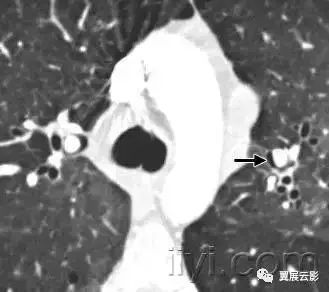

五、主肺动脉窗

解剖:纵膈的一部分,前界是升主动脉,后界是降主动脉,上界是主动脉弓,下界是左肺动脉,内侧为动脉韧带,外侧是胸膜和左肺。

平片和CT:正位胸片上,在主动脉弓以下,左肺动脉以上纵膈的弧形凹入。主动脉迂曲的时候,可以发生形状的改变。多种炎性病变和肿瘤性病变都可以导致主肺动脉窗的淋巴结增大。